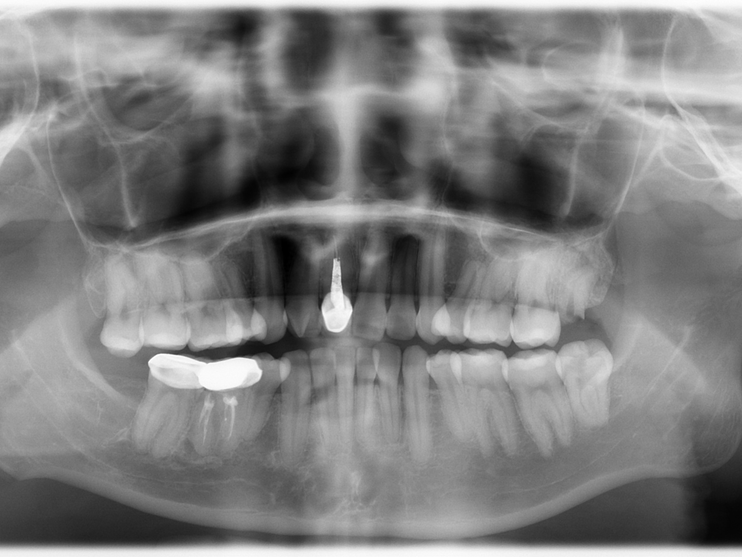

口腔全景牙片

颌面骨侧面全景

可以观察全口牙列,上下颌骨外伤、炎症、畸形等病变及周围组织的关系。